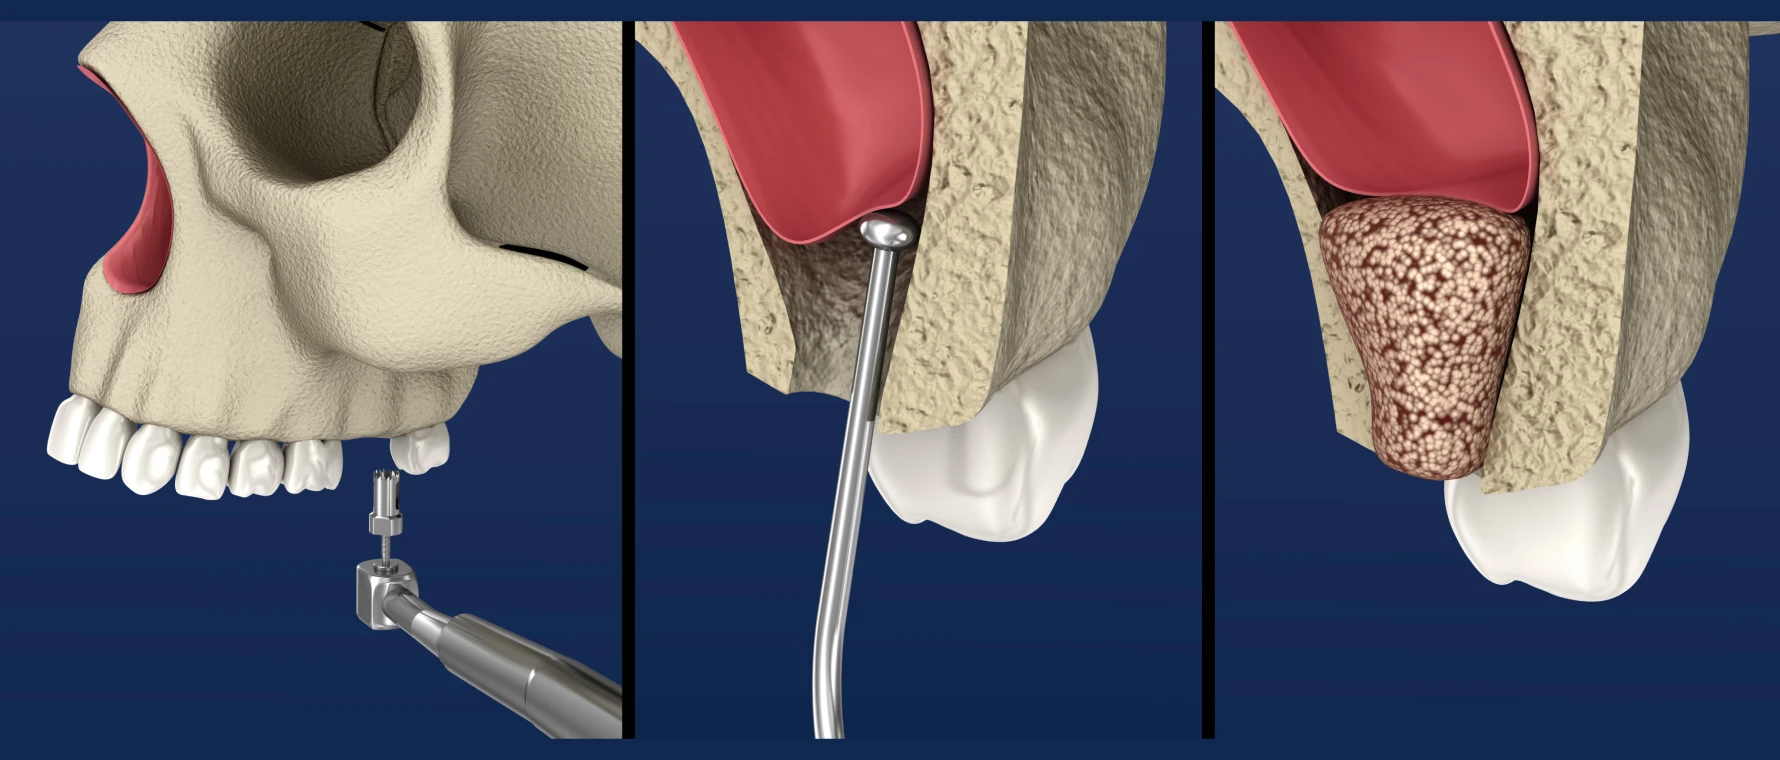

La voie latérale

C’est la méthode la plus répandue. Le praticien crée une fenêtre sur la paroi externe du maxillaire, soulève la membrane et insère le matériau osseux.

- Indiquée pour des pertes osseuses importantes.

- Permet un gain osseux significatif (jusqu’à 10 mm).

La voie crestale

Cette approche mini-invasive utilise le site de forage implantaire pour accéder au sinus. La membrane est délicatement soulevée par des ostéotomes ou des instruments spécifiques.

- Recommandée pour des déficits modérés.

- Peut être combinée à la pose simultanée de l’implant.

- Suites opératoires généralement plus simples.

En pratique, la voie latérale est privilégiée pour des déficits importants, tandis que la voie crestale est adaptée aux cas modérés.

Matériaux utilisés

Options disponibles

- Autogreffe (os du patient) : excellente intégration mais nécessite un second site opératoire.

- Allogreffe : os humain préparé par banque de tissus.

- Xénogreffe : matériau d’origine animale, très utilisé en implantologie.

- Substituts synthétiques : matériaux bioactifs (hydroxyapatite, phosphates de calcium).